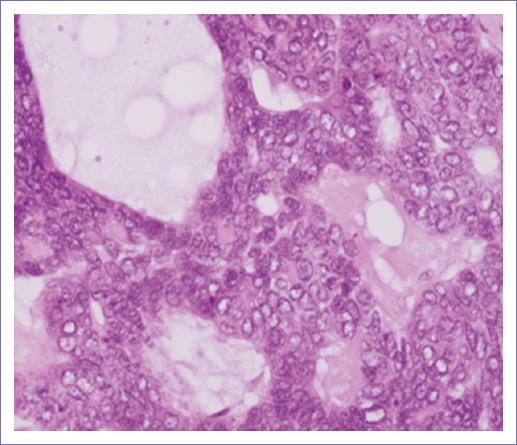

– Descripción microscópica. Los cortes histológicos examinados muestran la piel que presenta la epidermis sin alteraciones (Fig. 1); subyacente se observa tumor maligno de anexos cutáneos con patrón de crecimiento sólido, con proliferación de células de aspecto basaloide con núcleos vesiculosos. Pleomorfismo moderado y un índice mitósico de 4xCSF (40x) (Fig. 2). La neoplasia presenta formación de lúmenes intracitoplásmicos multifocales (Fig. 3). Los bordes del tumor son infiltrativos a nivel de dermis reticular (Fig. 4). No se identifica permeación vascular linfática. El lecho quirúrgico y bordes quirúrgicos no presentan lesión neoplásica.